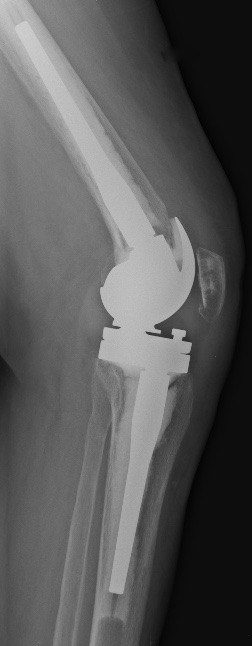

D. Prothèse à charnière (dernier recours si plus de ligament, reprises complexes, fractures sur prothèse)

Remplace les ligaments latéraux

charnière entre le fémur et le tibia (uniquement flexion et extension)

Quilles d’extension sont encore plus longues.